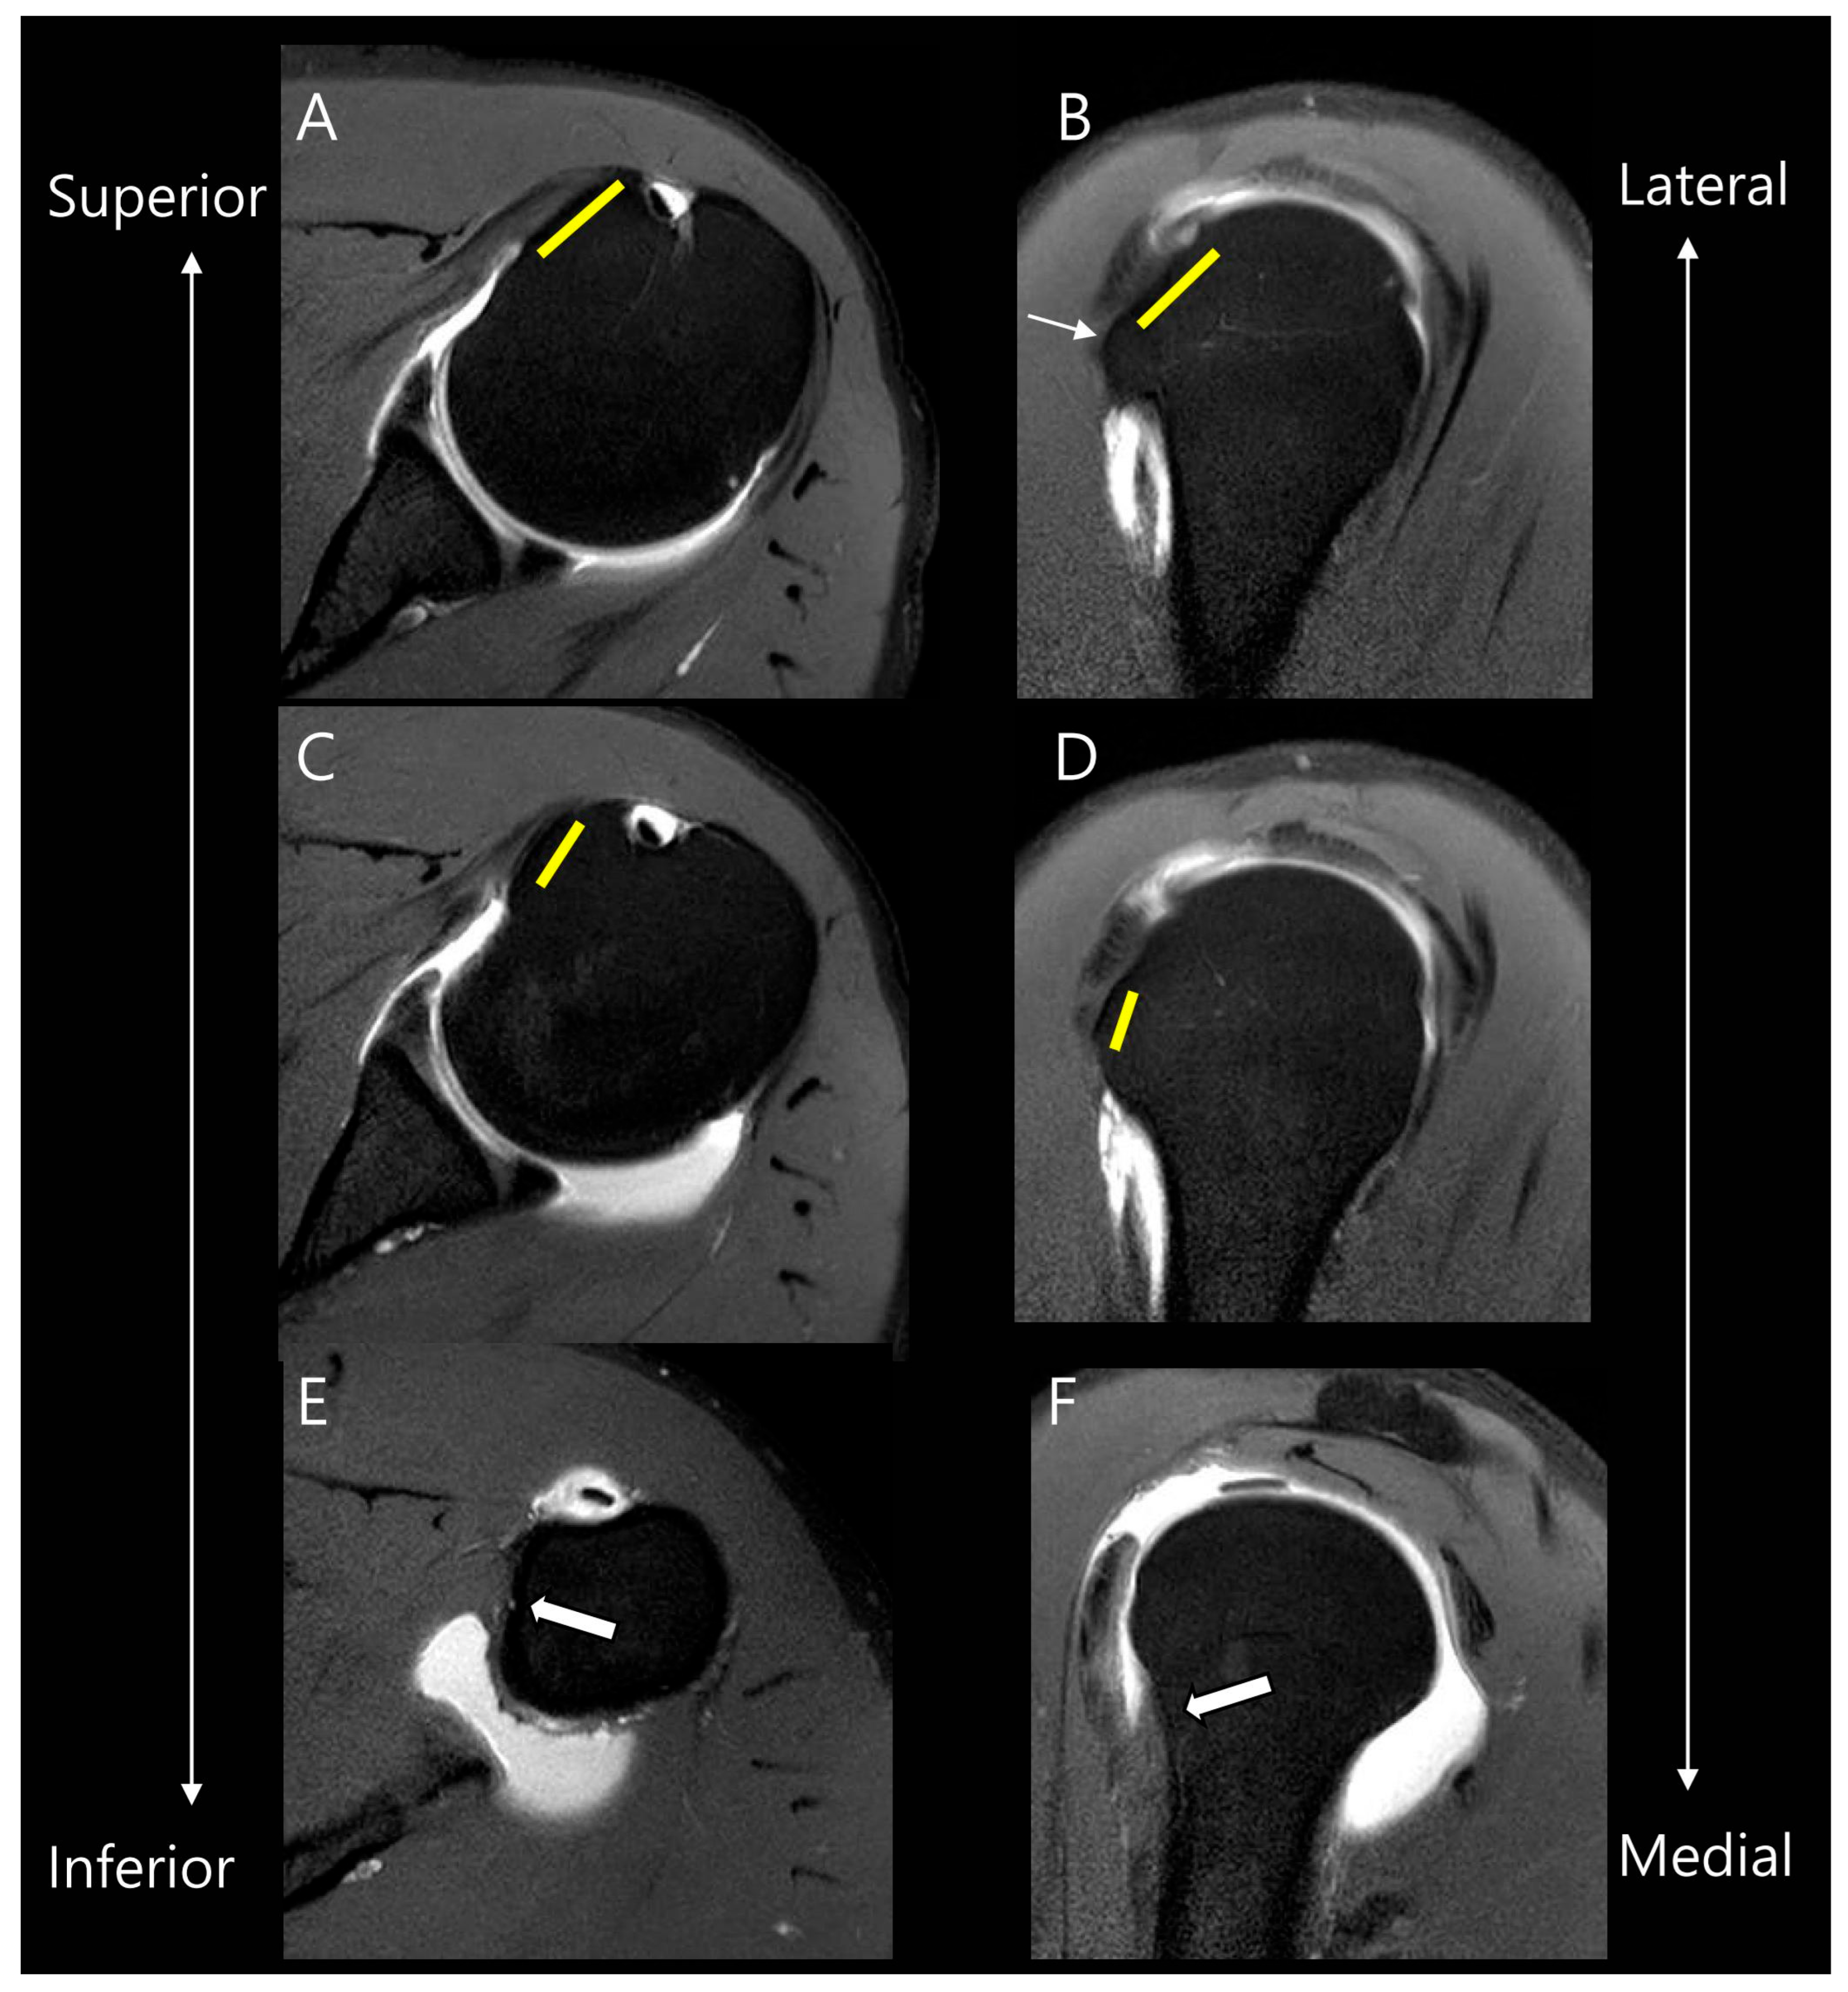

2.3. MRI Analysis

3.2. MRI Findings